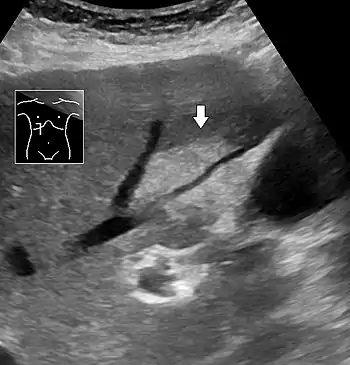

Medical imaging

Liver steatosis (fatty liver disease) as seen on CT

On X-ray computed tomography (CT), the increased fat component will decrease the density of the liver tissue, making the image less bright. Typically the density of the spleen and liver are roughly equivalent. In steatosis, there is a difference between the density and brightness of the two organs, with the liver appearing darker.[12] On ultrasound, fat is more echogenic (capable of reflecting sound waves). The combination of liver steatosis being dark on CT and bright on ultrasound is sometimes known as the flip flop sign.

On abdominal ultrasonography, steatosis is seen as a hyperechoic liver as compared to the normal kidney.